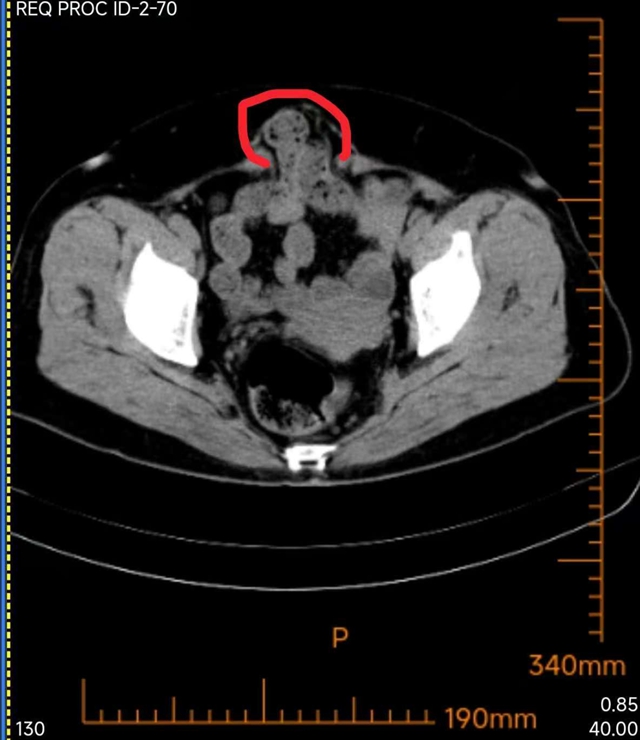

修补前

抱着一线希望,王阿姨来到西南医科大学附属中医医院普外·疝与腹壁外科就诊,黄恒医生接诊后耐心询问病史、细致查体,全面评估了王阿姨的病情,发现这个切口疝的棘手之处在于,缺损位于下腹部耻骨上,周围有膀胱、腹壁下血管等重要脏器,常规修补术难以固定补片,风险极高。